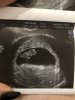

Nasze fasolki / USG